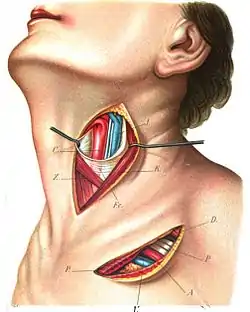

Superficial dissection of the left side of the neck, showing the carotid and subclavian arteries. | |

The fascia and middle thyroid veins. (Superior thyroid artery labelled at upper left.) | |